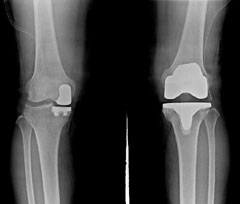

¹«¸­ °üÀý ¹Ý ġȯ¼ú(¿ÞÂÊ)°ú Àü ġȯ¼ú.

·Îº¿À¸·Î ¼Õ»óµÈ ¹«¸­ °üÀýÀÇ ÀϺθ¸ Àΰø°üÀý·Î ±³Ã¼ÇÏ´Â '·Îº¿ Àΰø°üÀý ¹Ý(Úâ) ġȯ¼ú'ÀÌ ±¹³» ¿¬±¸ÆÀ¿¡ ÀÇÇØ °³¹ßµÆ´Ù. '¹Ý ġȯ¼ú'Àº °üÀý Àüü¸¦ ±³Ã¼ÇÏ´Â 'Àü(îï) ġȯ¼ú'¿¡ ºñÇØ ¼ö¼úÀÌ ±î´Ù·Ó°í, ½ÇÆÐÀ²ÀÌ ³ô¾Æ Áö±Ý±îÁø °üÀý ÀϺΰ¡ ¼Õ»óµÈ ȯÀÚµµ ¾ÈÀüÇÑ 'Àü ġȯ¼ú'À» ¹Þ´Â °æ¿ì°¡ ¸¹¾Ò´Ù.

¾î¶² ¼ö¼úÀÌµç ¼Õ»ó ºÎÀ§¸¸ Á¦°ÅÇÏ´Â °ÍÀÌ ¿øÄ¢ÀÌÁö¸¸ Àΰø°üÀý ¼ö¼úÀÇ °æ¿ì¿£ ºÎºÐ ¼Õ»ó ȯÀÚµµ °üÀý Àüü¸¦ Á¦°ÅÇÏ´Â °æ¿ì°¡ ¸¹¾Ò´Ù. ¹Ý ġȯ¼úÀÇ °æ¿ì ³¢¿î Àΰø°üÀý°ú ¿ø·¡ °üÀýÀÌ ÇϳªÀÇ °üÀýó·³ ¿òÁ÷¿©¾ß Çϴµ¥ ºÎºÐ Àΰø°üÀýÀÇ À§Ä¡³ª Áß½ÉÃàÀÌ Á¶±Ý¸¸ Ʋ¾îÁ®µµ ¼ö¼úÀÌ ½ÇÆÐÇÒ °¡´É¼ºÀÌ ³ô¾Æ ÀÇ»çµéÀÌ ¹Ý ġȯ¼úÀ» ²¨·È´Ù°í ÇÑ´Ù. ÀÌ ¿øÀåÀº "¿ì¸®³ª¶ó ȯÀÚ´Â ´ëºÎºÐ ¾È¯´Ù¸®¿©¼­ °üÀýÀÇ ¾ÈÂʸ¸ ¸¶¸ðµÇ°í ¹Ù±ùÂÊÀº ¸ÖÂÄÇÑ °æ¿ì°¡ 30~40%Âë µÈ´Ù"¸ç "ÀÌ·± ȯÀÚ´Â ¾ÈÂÊ °üÀý¸¸ °¥¾Æ ³¢¿ì¸é µÇÁö¸¸ ¼ÕÀ¸·Î´Â ±×·¸°Ô Á¤±³ÇÏ°Ô Áß½ÉÃà°ú °¢µµ¸¦ ¸ÂÃß±â Èûµé¾î 'Àü ġȯ¼ú'À» ÇÏ´Â °æ¿ì°¡ ¸¹¾Ò´Ù"°í ¼³¸íÇß´Ù.